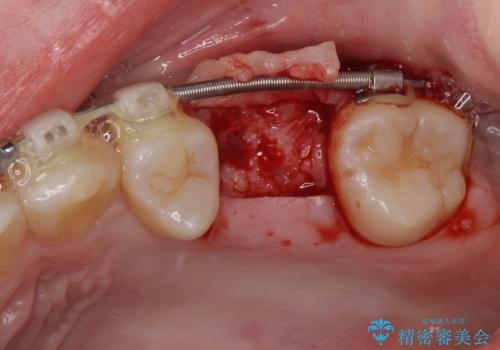

舌のトレーニングをしっかりと行っていただきながらワイヤー装置により矯正治療を行い、途中でインプラントを埋入し、矯正治療後に補綴治療を行うこととしました。

- 外科手術のため、術後に痛みや腫れ、違和感を伴います